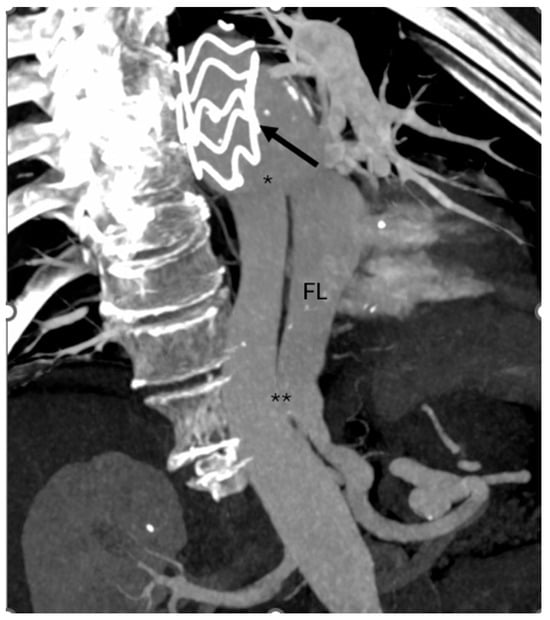

Finally, angiography confirmed proper device positioning, preserved visceral artery patency, and complete FL exclusion (Figure 5 and Figure 6).

Figure 5.

Final intraoperative angiography confirming the correct positioning of both the Terumo Aortic endograft (circle) and the FLOD (*).

Figure 6.

Pre- and post-procedural CTA reconstructions showing the treated aortic segment before (*) and after deployment of the endograft (**) and the FLOD (arrow), with evidence of effective false lumen exclusion.